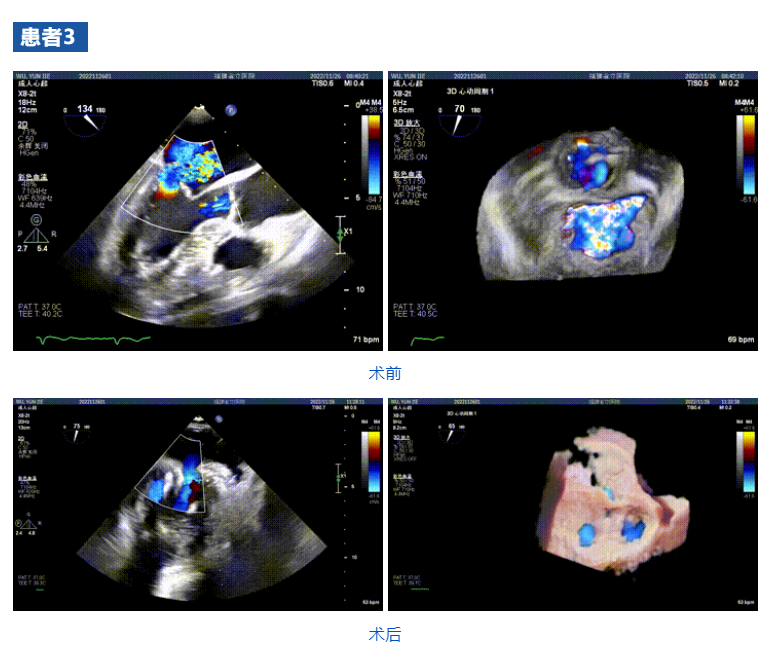

接受治療的三例患者均為器質性重度二尖瓣反流(DMR)患者,術前超聲提示二尖瓣后葉脫垂伴4+反流,左室舒張功能減退。郭延松教授攜同團隊成員陳新敬副教授和洪景宣、方明程、楊清勇主治醫師、心外科丁杭主任以及超聲科賴寶春、葉振盛主治醫師共同進行病情討論??紤]到患者高齡、基礎疾病多、STS評分高,為外科手術極高危患者,不適合進行外科開胸二尖瓣手術,因此決定為患者實施經導管緣對緣修復介入術(JensClip經導管瓣膜夾系統)。

在浙江大學醫學院附屬第二醫院王建安教授團隊的支持下,手術經股靜脈-房間隔入路,采用全身麻醉插管,在TEE和DSA引導下完成房間隔穿刺。置入JensClip瓣膜夾系統后,在左房調整瓣膜夾的位置和軸向,后進入左室,在TEE引導下捕捉二尖瓣前后瓣葉,并關閉瓣膜夾。經TEE反復確認手術效果后最終鎖定并釋放瓣膜夾。術后即刻超聲顯示瓣膜夾位置穩定,功能良好,二尖瓣反流由術前4+減少至微量,手術圓滿成功。